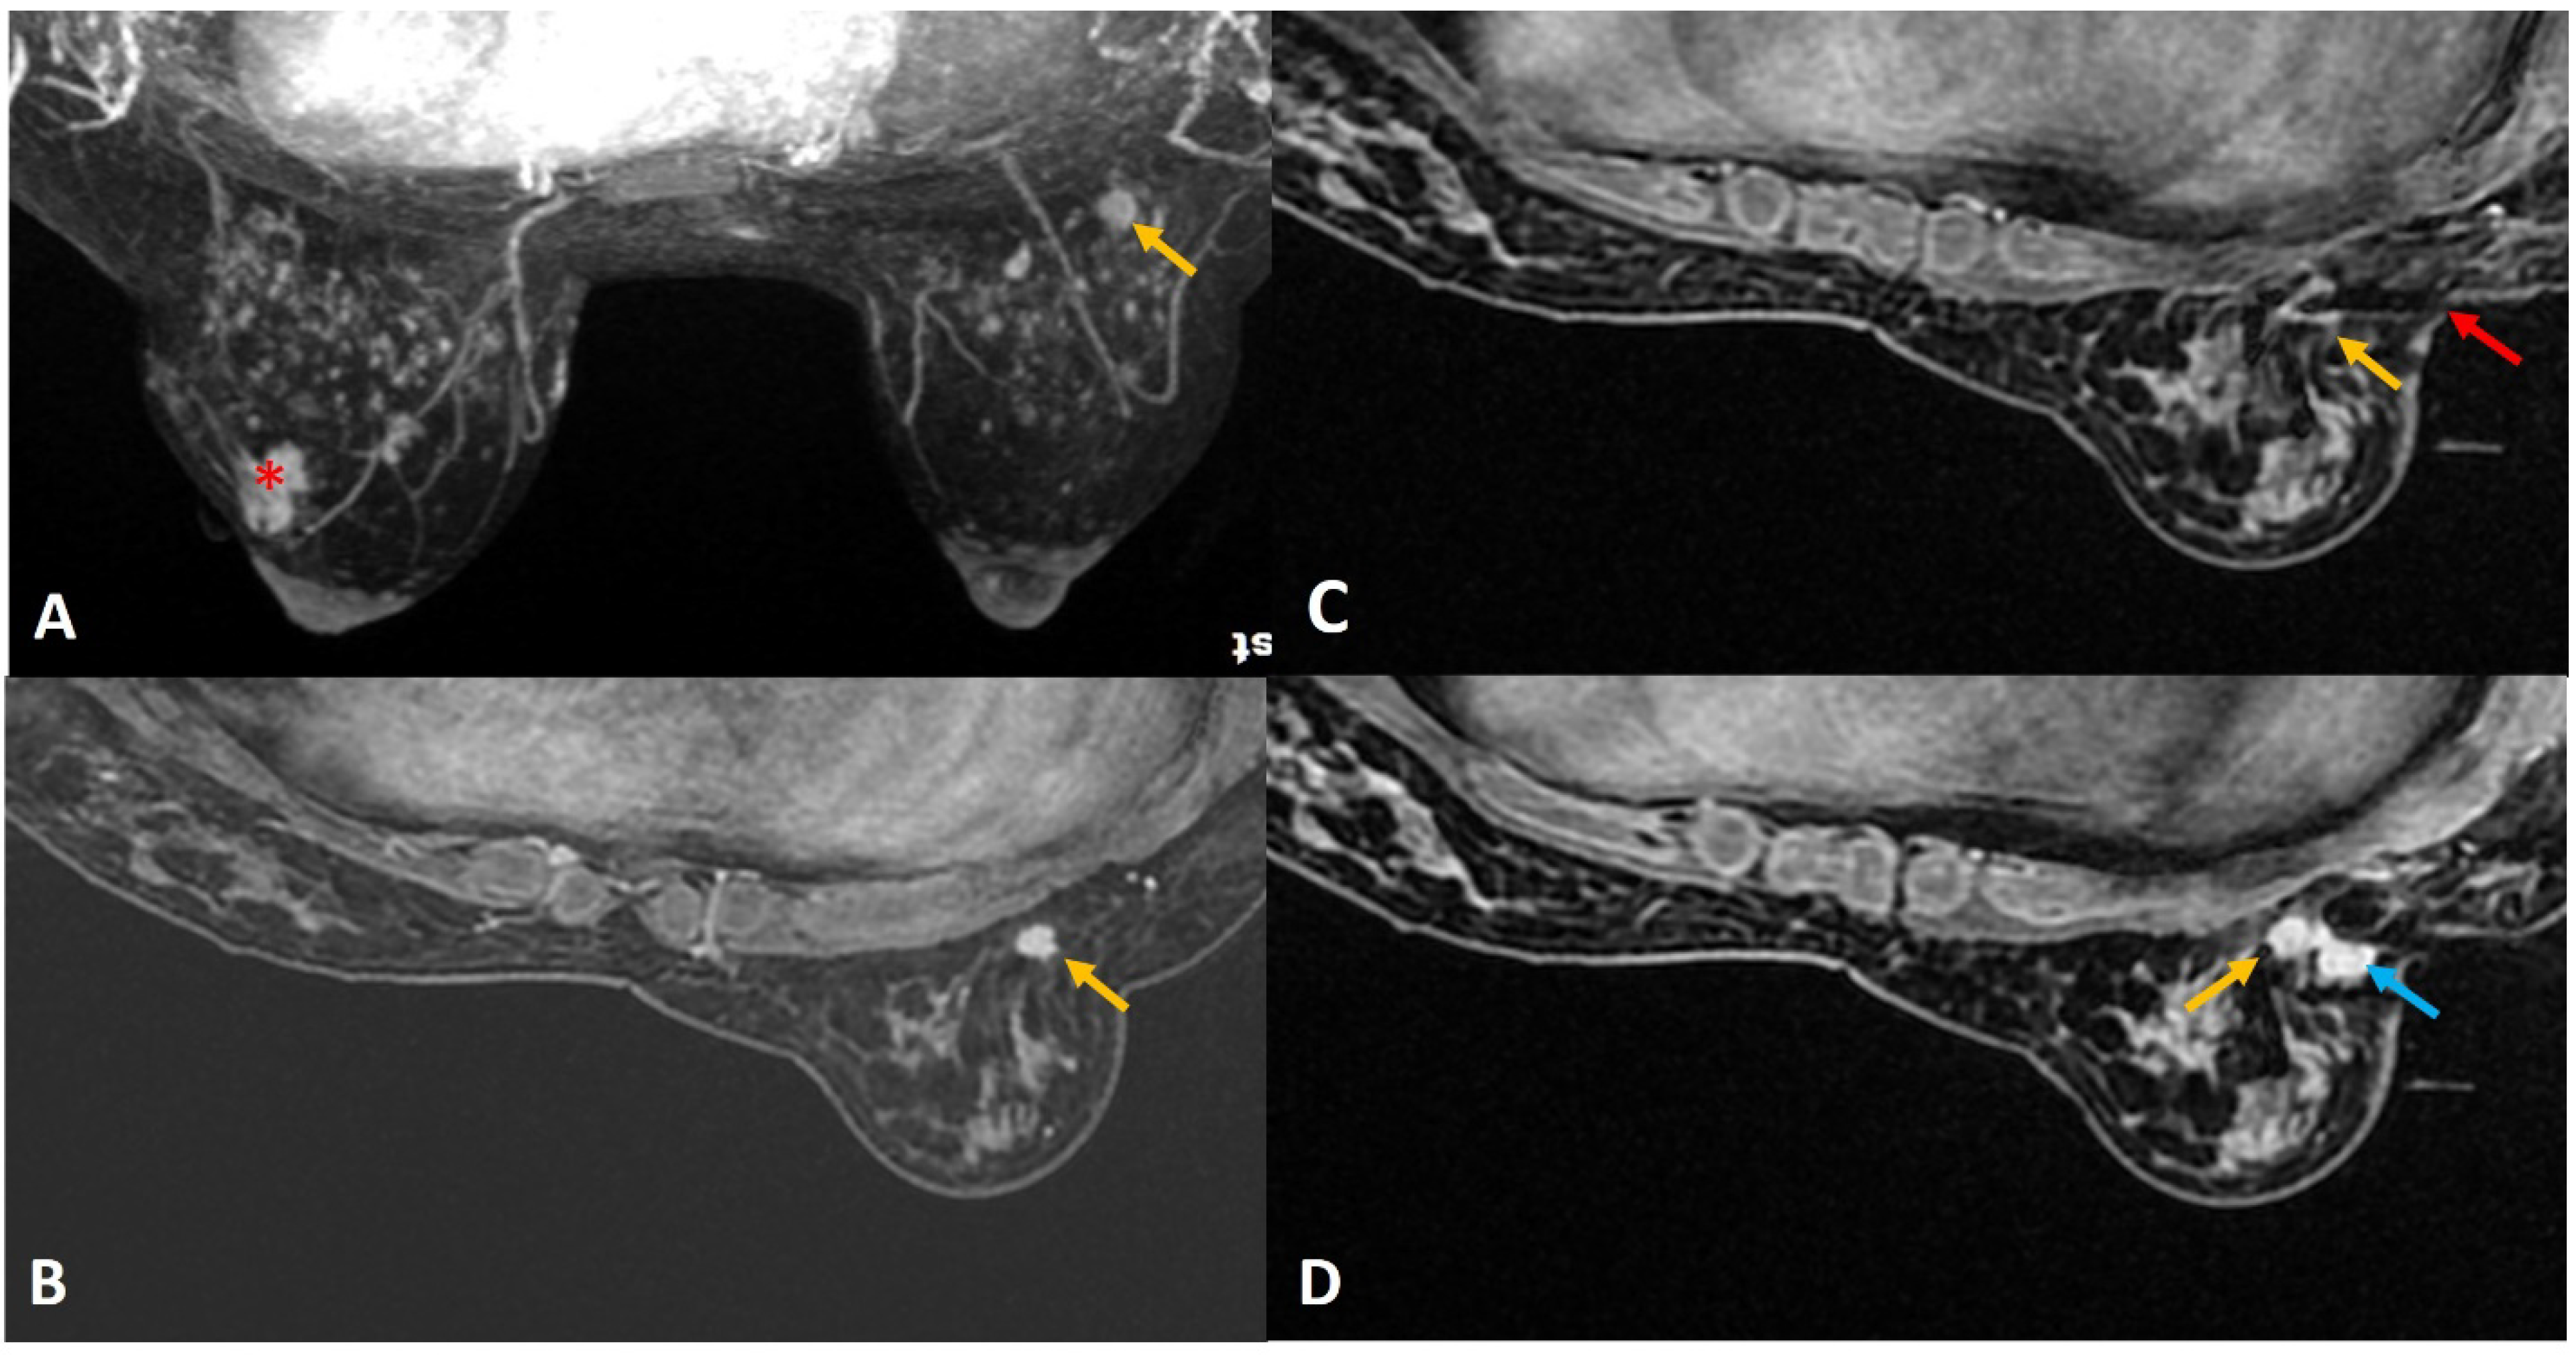

Figure 8.

(A). Screening MRI in a high-risk patient showed a new indeterminate focal non-mass enhancement (yellow arrow) in left breast. (B). During the biopsy, the enhancing lesion (yellow arrow) was seen compressed and pushed along posterior aspect. (C). The lesion (yellow arrow) was displaced medially by the obturator of the biopsy guide. (D). The needle was pushed beyond the target and then withdrawn to correct depth (yellow arrow). This strategy helped to place the needle well in relation to the target lesion. (E). Post-biopsy hematoma (yellow arrow) is noted. (F). Follow up MRI after a year confirmed appropriate location of the marker clip with lack of enhancement in this region (yellow arrow). The histology of this lesion was reported as sclerosing adenosis.